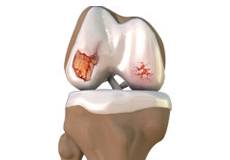

Articular Cartilage and Menisci of the Knee

Movement of the bones causes friction between the articulating surfaces. To reduce this friction, all articulating surfaces involved in the movement are covered with a white, shiny, slippery layer called articular cartilage. The articulating surface of the femoral condyles, tibial plateaus and the back of the patella are covered with this cartilage. The cartilage provides a smooth surface that facilitates easy movement.

Within the knee joint, between the femur and tibia, are two C-shaped cartilaginous structures called menisci. Menisci function to provide stability to the knee by spreading the weight of the upper body across the whole surface of the tibial plateau. The menisci help in load-bearing i.e. it prevents the weight from concentrating onto a small area, which could damage the articular cartilage. The menisci also act as a cushion between the femur and tibia by absorbing the shock produced by activities such as walking, running and jumping.

The joint surface is covered by a smooth articular surface that allows pain-free movement in the joint. Arthritis is a general term covering numerous conditions where the joint surface or cartilage wears out. This surface can wear out for several reasons; often the definite cause is not known. Arthritis often affects the knee joint. When the articular cartilage wears out, the bone ends rub on one another and cause pain.

Osteoarthritis also called degenerative joint disease, is the most common form of arthritis. It occurs most often in older people. This disease affects the tissue covering the ends of bones in a joint (cartilage).In a person with osteoarthritis, the cartilage becomes damaged and worn out causing pain, swelling, stiffness and restricted movement in the affected joint.